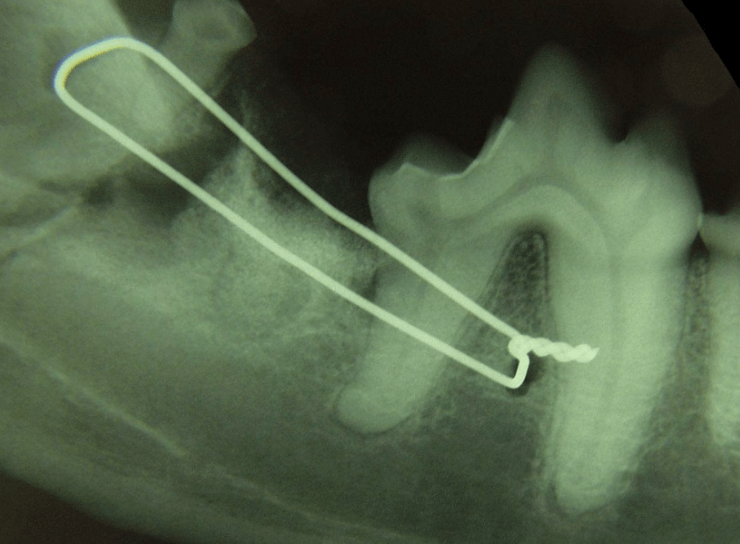

This procedure is typically done in the rest of the skeleton, but can be used in the mouth in cases of fracture

What is osseous wiring?